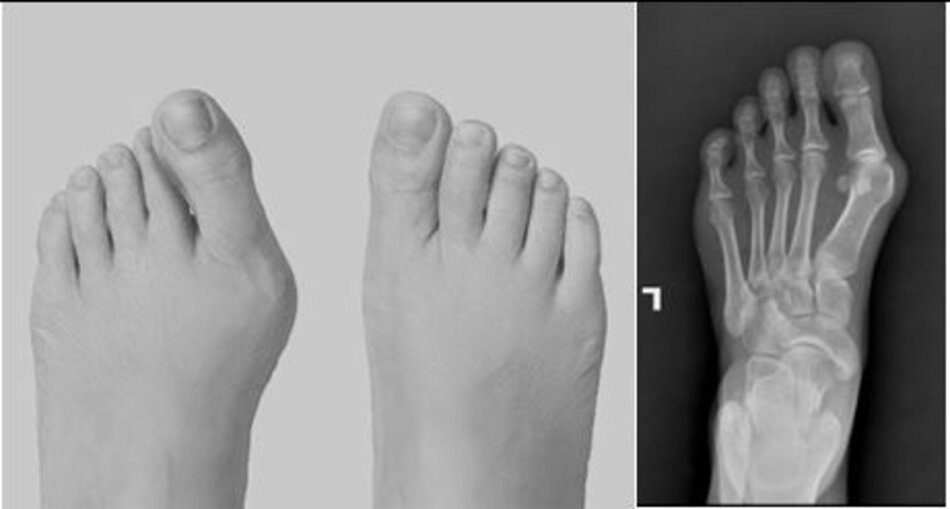

Vẹo ngoài ngón I

Hình ảnh bàn chân trái và X-quang bàn chân trước mổ

Hình ảnh bàn chân trái và X-quang bàn chân sau chỉnh hình vẹo ngón

Hình ảnh bàn chân trái và X-quang bàn chân sau chỉnh hình vẹo ngónHình ảnh bàn chân trái và X-quang bàn chân sau chỉnh hình vẹo ngón

Phẫu thuật chỉnh hình Vẹo ngoài ngón I bàn chân